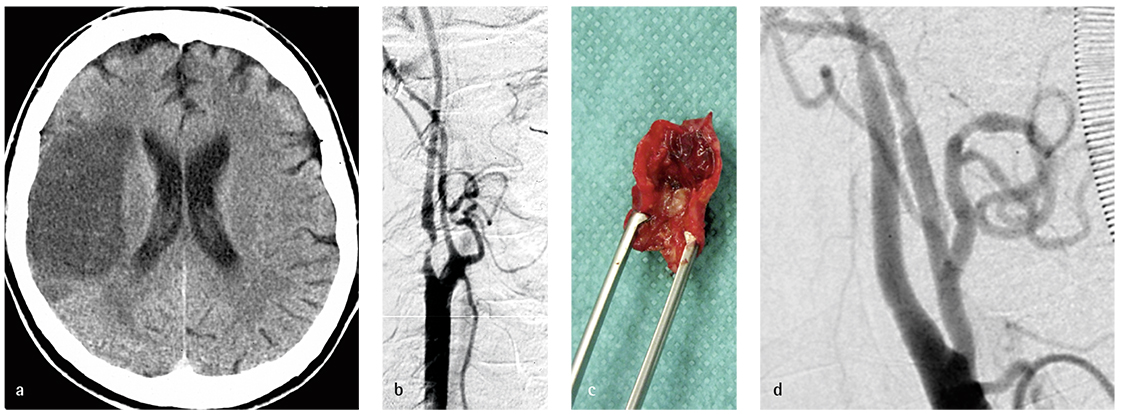

Abbildung 2: 76-jähriger Mann mit Infarkt der Arteria cerebri media rechts (a) bei hochgradiger Karotisstenose rechts (Katheterangiografie, b) Karotis-TEA nach 14 Tagen. Intraoperativer Nachweis einer hochgradigen atherosklerotischen Stenose mit frischen Thrombusauflagerungen (c). Intraoperative Angiografie zur Kontrolle der Strombahn nach Eversions-TEA (d).